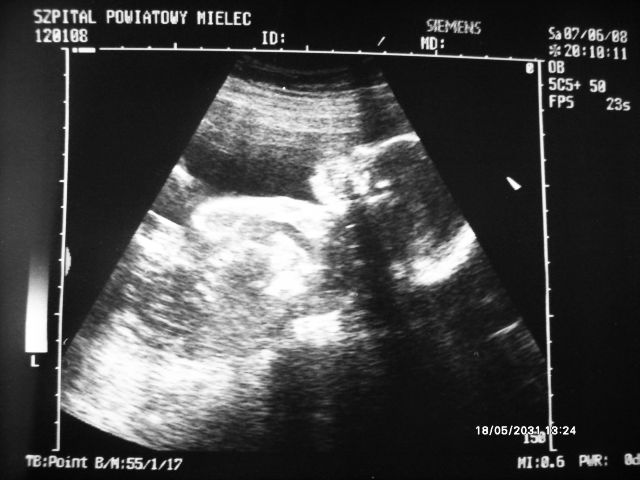

A oto moja mała:)

Załączniki

• 01USG.JPG

01USG.JPG

56,3 KB · Wyświetleń: 49

• 02USG.jpg

02USG.jpg

77,3 KB · Wyświetleń: 54

Malena śliczne zdjątka bąbelka.

Malene81 śliczne fotki jak ładnie widać mam bardzo podobne USG laury:tak: